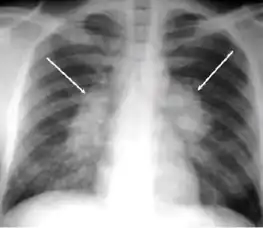

Chest x-ray of pleural thickening post-primary tuberculosis

1. Pleural thickening - Irregularity or abnormal prominence of the pleural margin, including apical capping (thickening of the pleura in the apical region). Pleural thickening can be calcified.